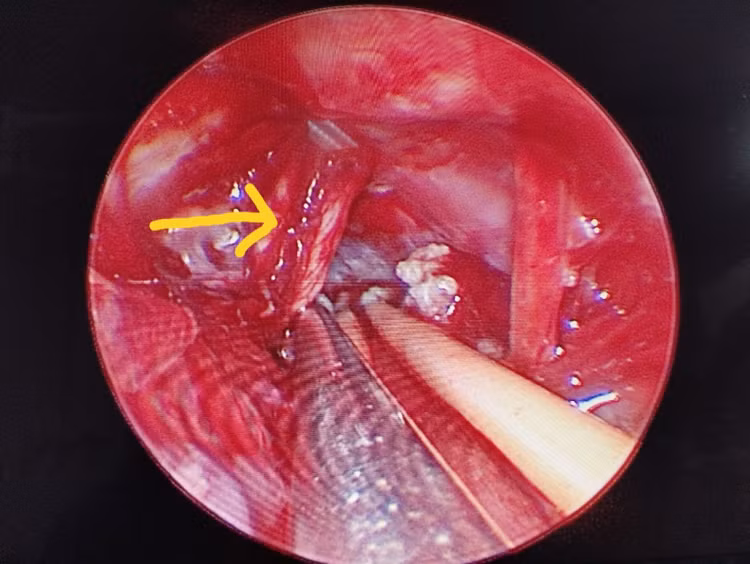

Dưới sự hỗ trợ của hệ thống phẫu thuật vi phẫu và nội soi hỗ trợ, Ekip phẫu thuật của Ths.BS Giang Lộc Anh (Khoa Ngoại – Thần kinh lồng ngực, Bệnh viện Bãi Cháy) đã tiến hành mở xương sọ sau xoang sigma, lấy u tối đa, giải ép xung đột mạch máu - thần kinh V. Ca phẫu thuật diễn ra an toàn, đảm bảo cầm máu tốt và bảo tồn cấu trúc não lành và các dây thần kinh quan trọng. Sau 7 ngày, bệnh nhân phục hồi tốt, giảm đau rõ rệt, không ghi nhận biến chứng và được xuất viện.

Xung đột mạch máu và thần kinh V trên hệ thống nội soi

Hiện nay, với sự hỗ trợ đắc lực của các trang thiết bị hiện đại như hệ thống vi phẫu, hệ thống nội soi, phẫu thuật viên có thể quan sát phẫu trường vùng góc cầu – tiểu não, vùng gần thân não, các vị trí xung đột mạch máu – thần kinh dưới nhiều góc độ hơn, rõ ràng hơn.